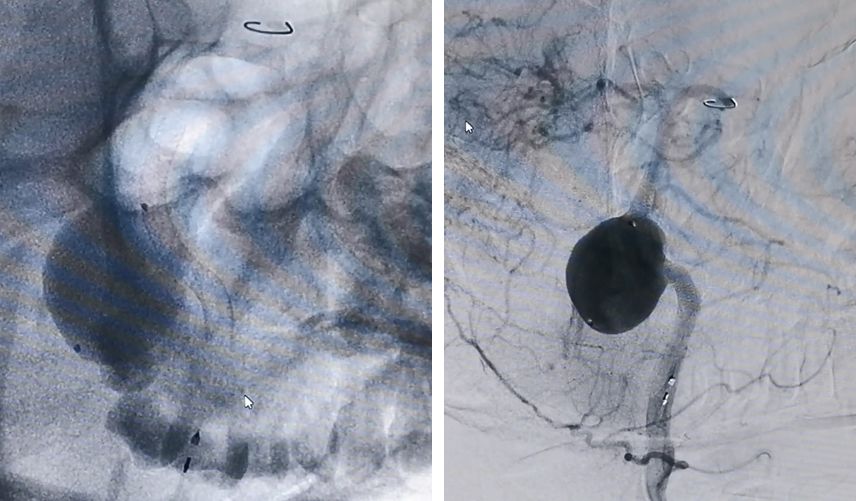

PED释放完毕,位置及贴壁良好,左椎-基底动脉血运通畅,未填弹簧圈,即可见到瘤腔内造影剂的滞留,说明支架贴壁良好,起到了良好的重建作用

经右椎动脉逐步填塞大弹簧圈进入动脉瘤(Microplex-18系列),逐步将动脉瘤疏松填塞。期间微导管头端受到弹簧圈阻力,会缓慢回撤,此时不必刻意调整微导管再次深入动脉瘤腔内,因为我们最主要目的不是严密填塞动脉瘤—那是PED的任务—而是闭塞右侧椎动脉

最后,用小弹簧圈完全闭塞右侧椎动脉(PICA以远)

左椎动脉造影显示椎-基底动脉及远端血管通畅,动脉瘤虽然部分显影,但是PED最终会让动脉瘤完全修复。